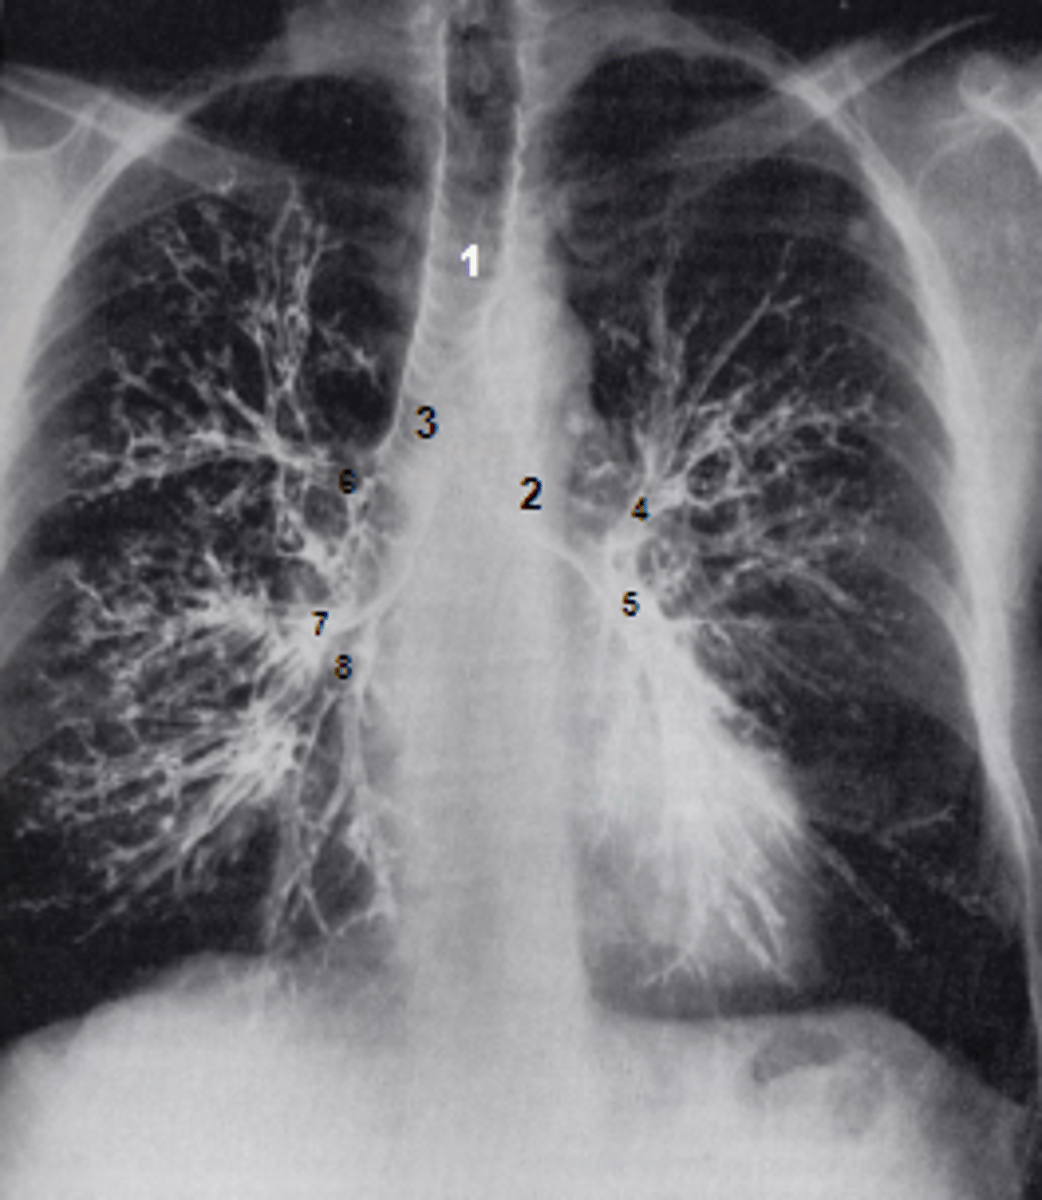

1

at what number is the trachea

2

at what number is the left main bronchus

3

at what number is the right main bronchus

4

at what number is the left superior lobar bronchus

5

at what number is the left inferior lobar bronchus

6

at what number is the right superior lobar bronchus

7

at what number is the right middle lobar bronchus

8

at what number is the right inferior lobar bronchus